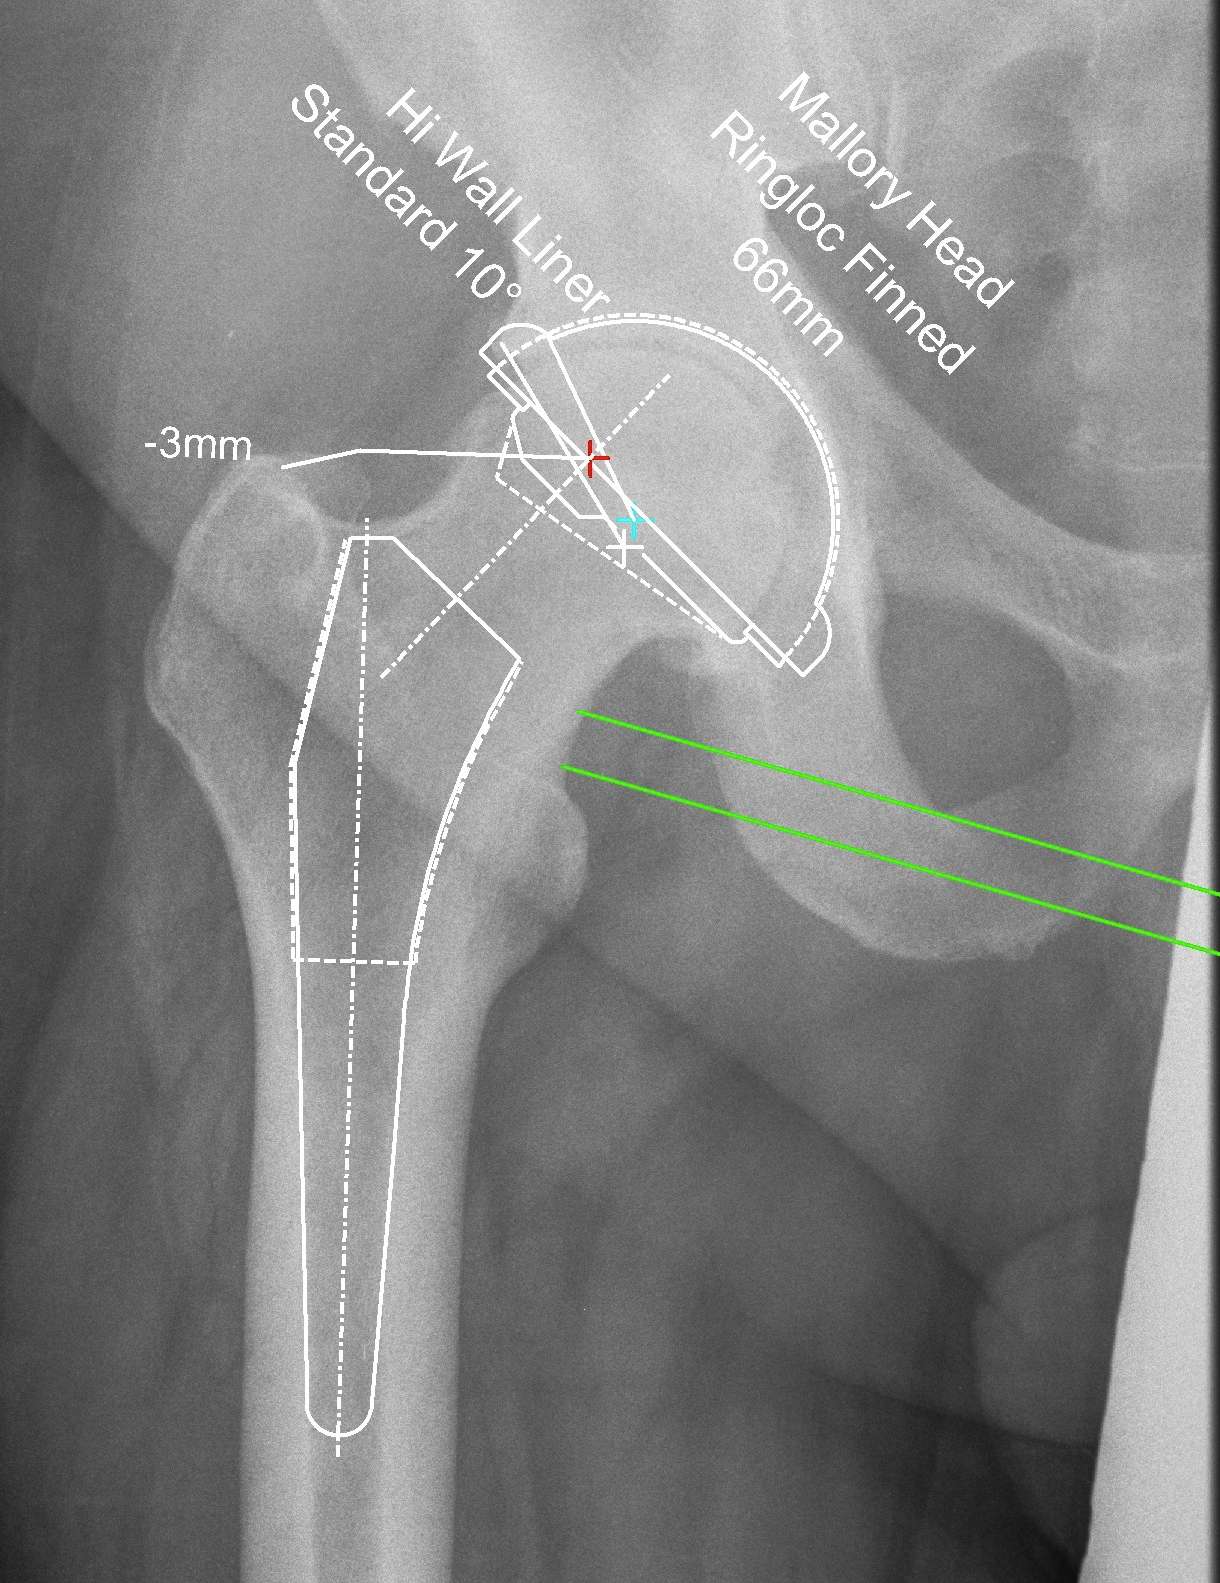

Zimmer Online One Planner